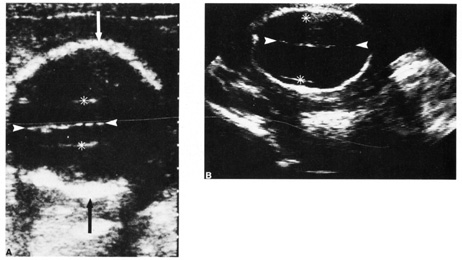

Diagnostic ultrasound is widely used in the assessment of pregnancy and the fetus. Although clinical benefits of routine ultrasonography during pregnancy have not been established, approximately 70% of pregnancies in the United States undergo ultrasound evaluation.30 Because most instruments used in diagnostic ultrasonography produce energies no greater than 10 to 20 mW cm2 (safety defined as less than 100 mW cm2), ultrasound is considered generally safe. No harmful biologic effects on instrument operators, pregnant women, fetuses, or other patients have been found. Infants exposed in utero have shown no significant differences in birth weight or length, childhood growth, cognitive function, acoustic or visual ability, or rates of neurologic deficits (see Fig. 6).

Fig. 6. A: First-trimester twin intrauterine gestations. Ultrasound examination of the pregnant uterus (arrowheads) shows the “owl eyes” characteristic of early twin pregnancies. B: Maternal urinary bladder. (Courtesy of Alfred B. Kurtz, MD)

Fetal number (Fig. 6)